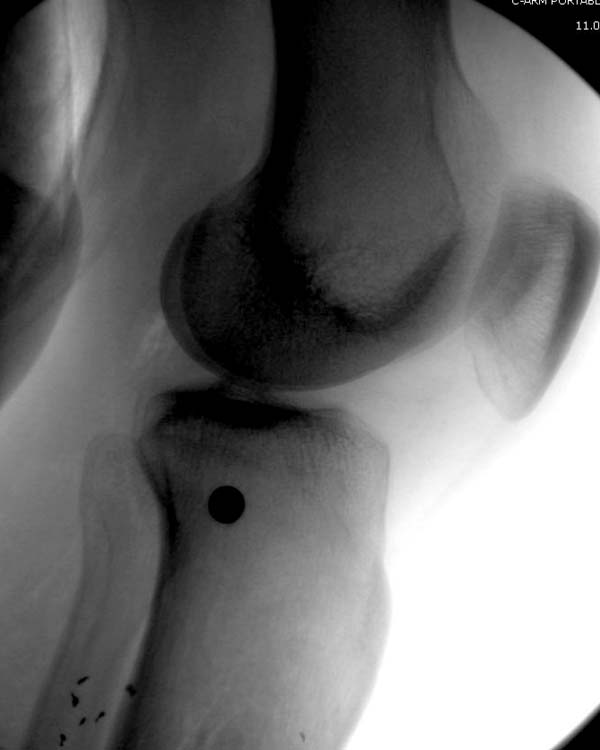

Имя     : 01 gsw injury med wound.jpg

Url     : http://weborto.net:8080/pipermail/ortho/attachments/20150717/eea7e369/attachment-0013.jpg